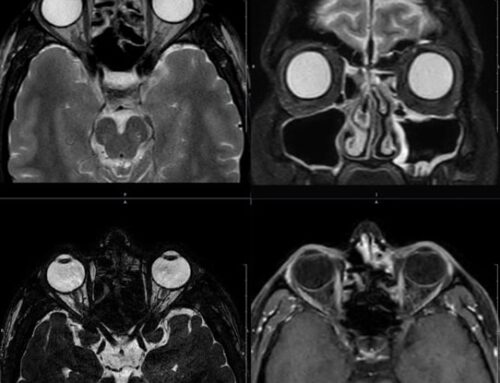

O exame é frequentemente solicitado em casos de câncer de cérebro, mama, fígado, pâncreas, próstata, colo do útero e reto, além de tumores ósseos e demais estruturas da face e pescoço. Em muitos desses casos, a ressonância oferece informações mais detalhadas do que outros exames de imagem.